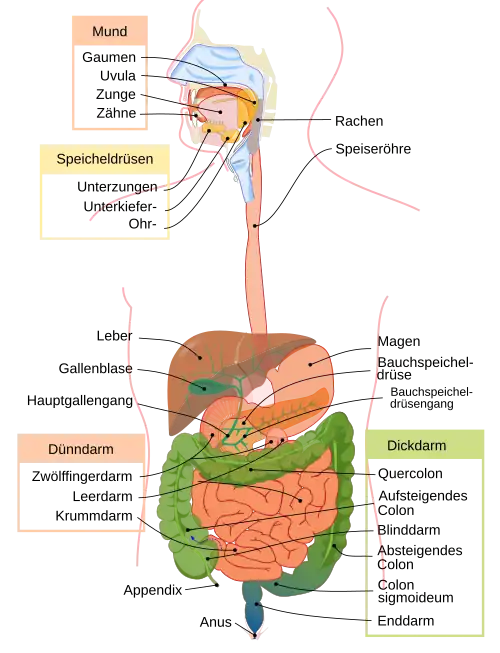

Colon des Menschen

|

|

Der menschliche Dickdarm:

|